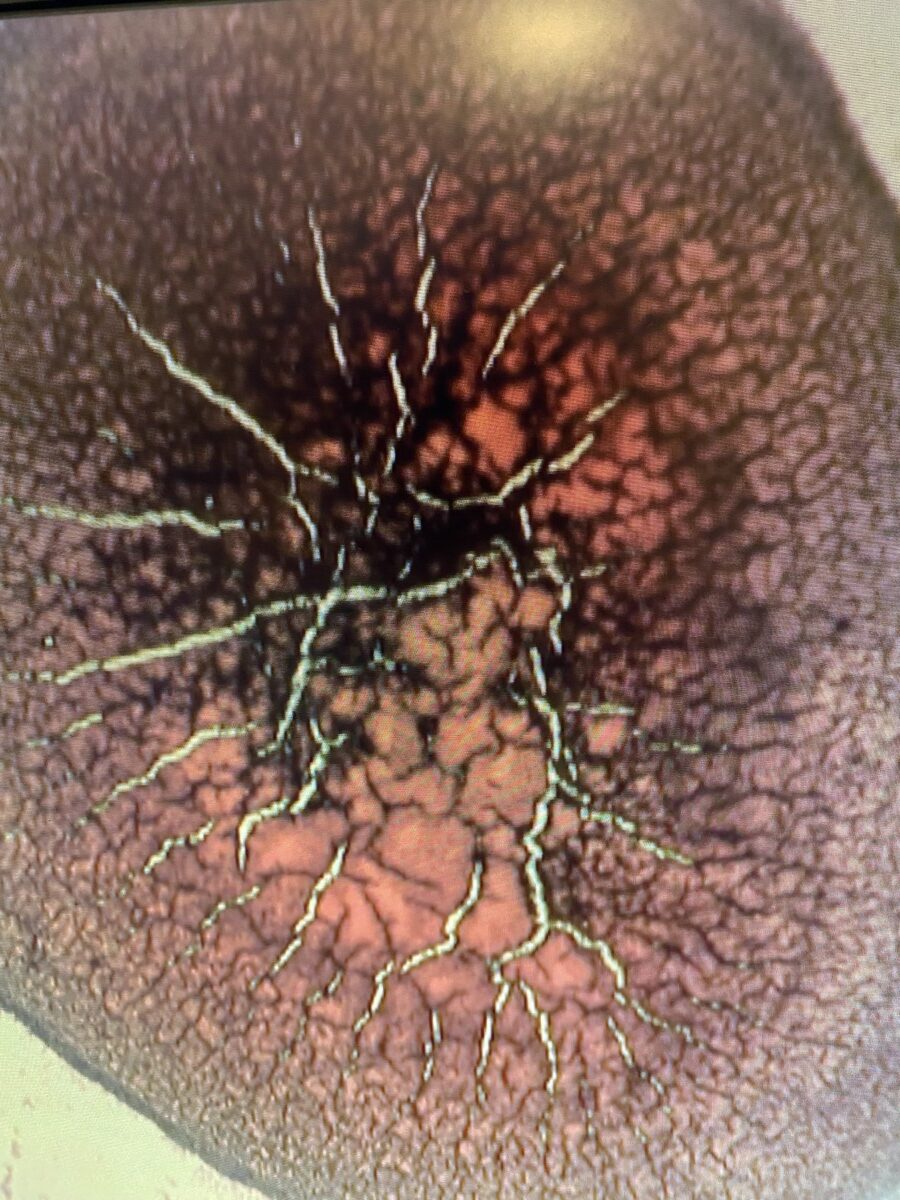

December 2023 Demineralization and inflammation – EMF overload? HAARP?

In the past few months we have observed something very unusual in the dry blood sample of most of our clients. We have seen high level of what is called “calcium spokes” (white spokes radiating out) and high level of inflammation characterized by raised red bumpy areas. These where on most of the layers on the sample (2 to 8).

These morphologies are not rare but what is highly unusual is that most of our clients are showing both of these signs in their dry blood. We are suspecting that an external factor of unknown origin is creating a high level of oxidative stress and inflammation. Our personal guess is that it could originate due to some form of EMF (Electro magnetic frequency, microwave radiation, 5G) causing a major disturbance in our biological systems and bio terrain. Please clink on this link to view this very powerful and informative youtube video about HAARP and how it can affect everything including human beings.

The blistering is associated with heart and circulation problems, stress on the heart, possible arrhythmia, hypertension indicating extreme inflammation.

White radial spokes indicate mineral deficiencies /electrolytes/ possibly leaching calcium from bones as the body is attempting to correct acidic terrain and electrolytes imbalances.